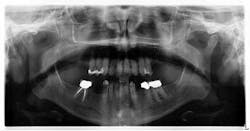

Sara (name changed) was 37 years old when she first walked into my office because of a toothache (figure 1). A review of her health history included: Crohn’s and celiac disease, depression, asthma, and several surgeries; her prescriptions included: antiseizure, depression, insomnia, and OCD (obsessive-compulsive disorder) medications. The cocktail of these drugs were a necessary evil; dry mouth ensued and rampant caries took over. Due to lack of financial resources, instead of restoring her teeth she had them removed one by one, including the tooth she came in about that day (No. 13).

After a complete assessment, it was apparent that Sara’s options were limited with her existing dentition. The caries present were large and apple-cored around the teeth, making the long-term restorative prognosis questionable or guarded at best (figures 2-5). Several key teeth for partial abutments were either missing or grossly carious.